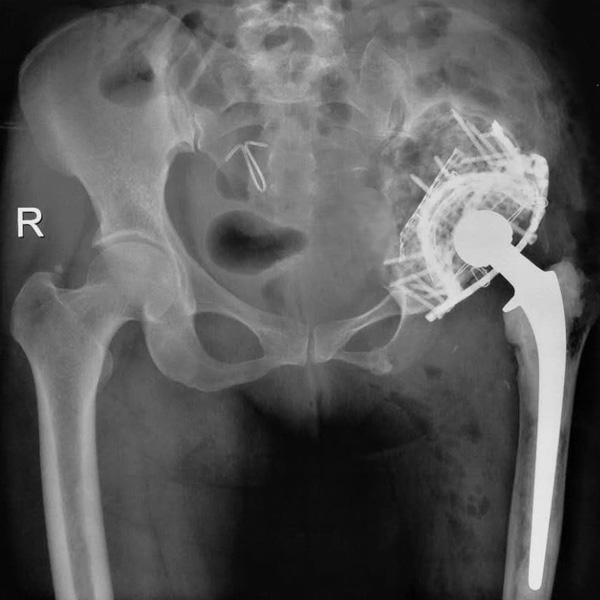

髖關(guān)節(jié)翻修

患者蘇某,女性,11年前因“左髖關(guān)節(jié)屈曲攣縮畸形”行左側(cè)人工全髖關(guān)節(jié)置換,近來感覺左髖關(guān)節(jié)疼痛,不敢行走,經(jīng)“攜生醫(yī)療平臺”就診于哈......